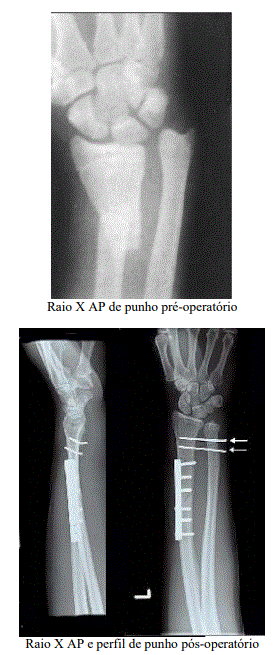

Uma paciente de 10 anos de idade, obesa, destra dominante, sofreu queda de bicicleta com consequente trauma e fratura do terço distal do rádio e luxação da articulação radioulnar distal. Foi submetida à redução e fixação cruenta da fratura para osteossíntese com placa e parafusos e fios de Kirschner, conforme imagem. Ficou imobilizada por seis semanas com gesso em posição de supinação máxima. Após a retirada da imobilização gessada, foi encaminhada para fisioterapia, pois exibia uma hiperalgesia e distonia, não sendo capaz de sustentar absolutamente nenhum peso na extremidade superior direita, e o punho e a mão encontravam-se lustrosos, inchados e vermelhos. Observava-se, ainda, importante restrição da amplitude de movimento para os movimentos de pronação da radioulnar e da flexão- extensão do punho. Dor classificada em 9/10 pela escala analógica visual, e a paciente e não tolerava a aplicação de crioterapia no local.